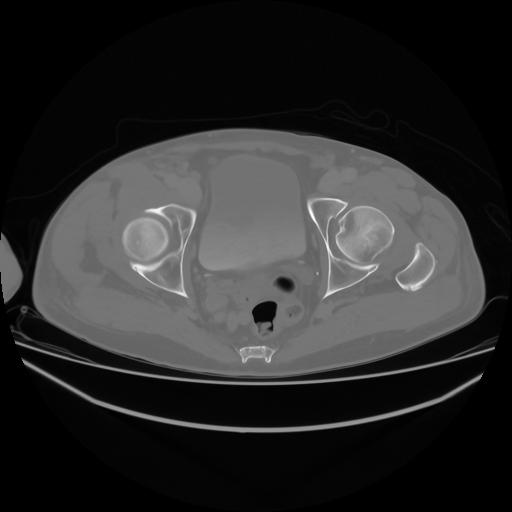

4 CUERPO,CE,Axial,3.0,CUERPO,,